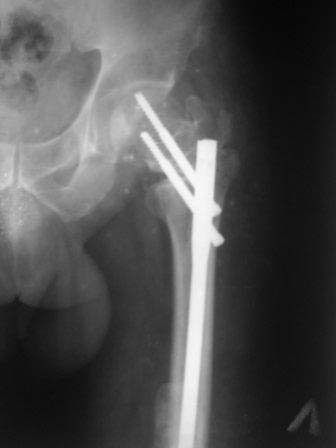

ЭОП унас нет, больной оперирован тогда, 35 дней назад, во время наркоза определена патологическая подвижность в вертельной обл, поэтому произведена

остеотомия с исправлением угла, антеградный БИОС ,универсальный стержень ChM. Рентген снимки свежие фас и аксиальная. Пациент ходит с двумя костылями, ногу частично нагружает, лежа выпрямленную ногу поднимает.